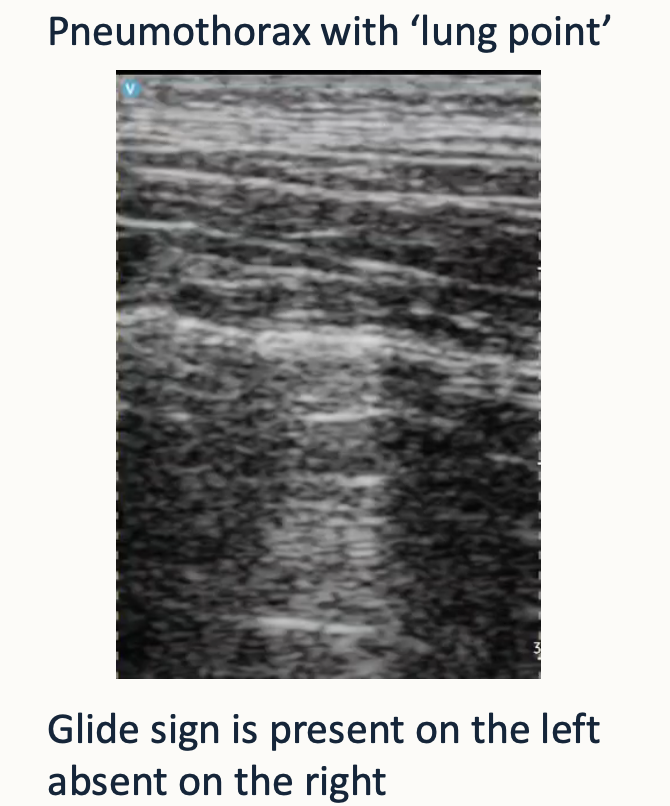

18

Q

What is going on in this lung ultrasound

A

How well did you know this?